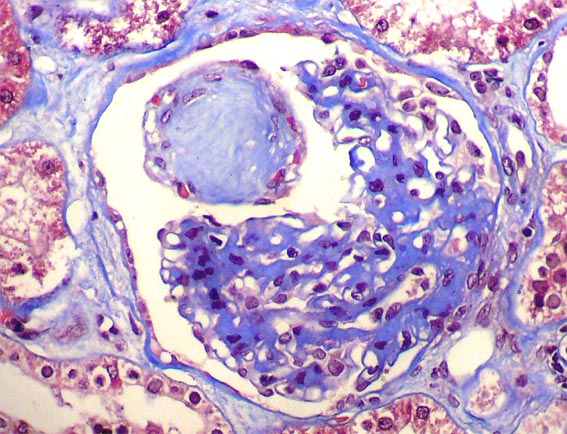

Figura 5.

Glomerulosclerosis global: 5 de 145. Tricrómico de Masson, X400.

Figura 6.

Hialinosis en aferente y eferente. PAS, X400.